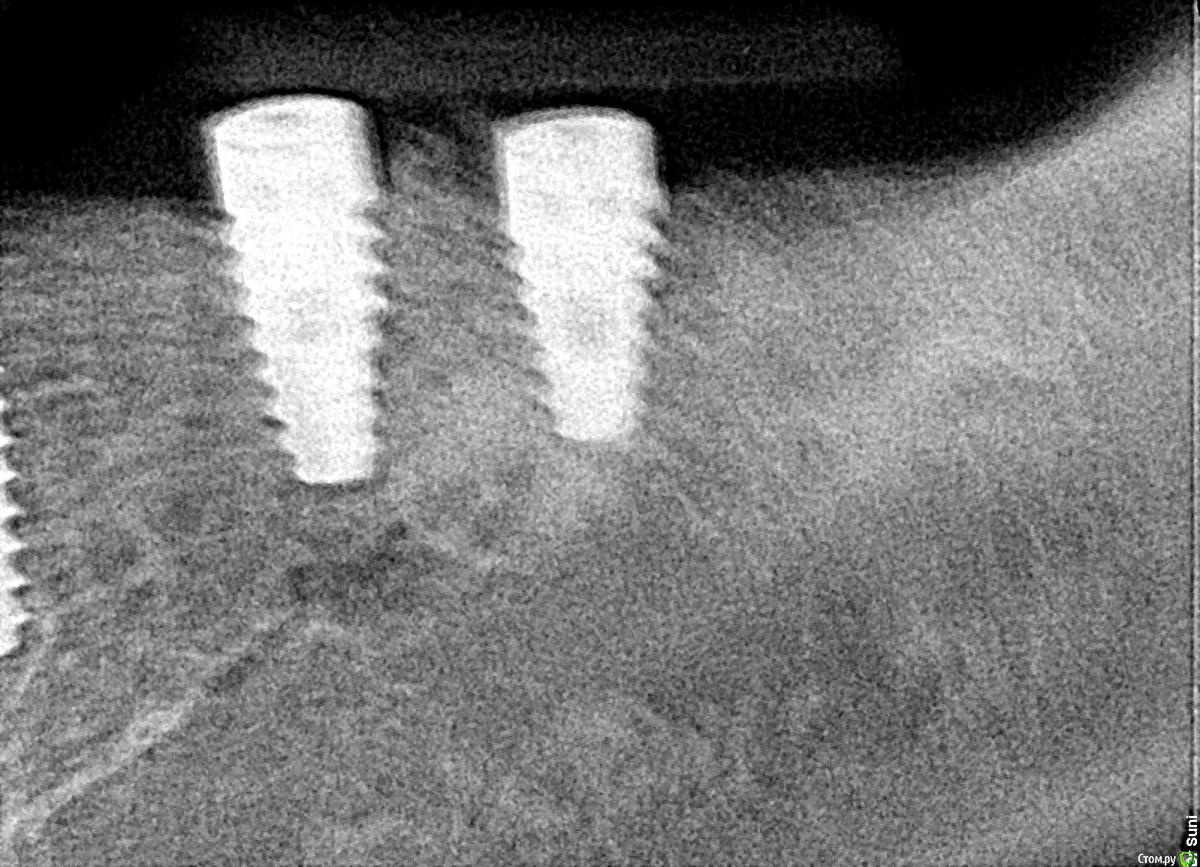

bilal Опубликовано 25 декабря, 2017 Поделиться Опубликовано 25 декабря, 2017 добрый день. 2 месяца назад ставил 6 имплантов на нижней челюсти, сегодня сделал рентген, вокруг шейки двух имплантов такая картина.может надо было изначально заглубить побольше.как вы думаете, кокой прогноз? и какие дальнейшие действия? у дального импланта просвечивала заглушка, ставил фдм. Ссылка на комментарий

bilal Опубликовано 25 декабря, 2017 Автор Поделиться Опубликовано 25 декабря, 2017 снимки на момент имплантации и сегодня Ссылка на комментарий